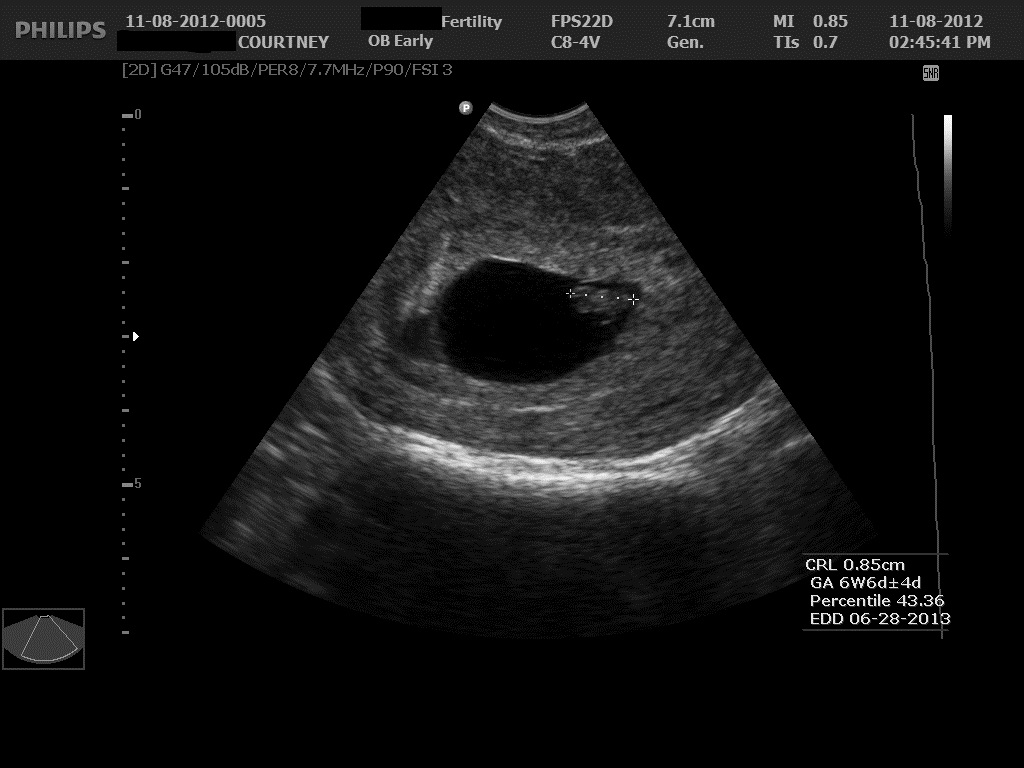

Ultrasound 2 November 12, 2012 by Courtney Leave a comment ← Previous Image Next Image → 6w4d – CRL of 8.5mm Like Loading...